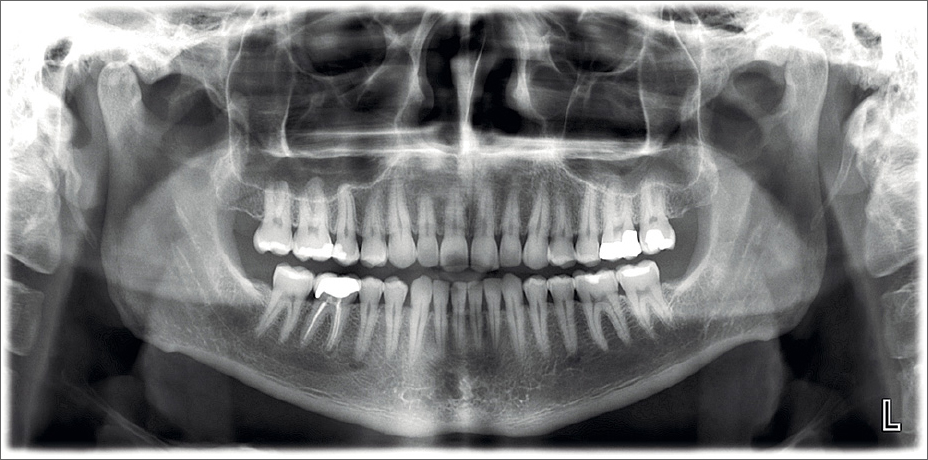

When it comes to diagnosing dental issues with precision, an Orthopantomogram (OPG), commonly known as a dental X-Ray, plays a pivotal role. This advanced imaging technique provides a comprehensive, panoramic view of your entire mouth, including teeth, jawbones, and surrounding structures, enabling dentists to detect problems such as cavities, impacted teeth, gum disease, or jaw abnormalities with unmatched accuracy.

An OPG, or panoramic dental X-Ray, creates a two-dimensional image of the entire oral cavity.

Unlike traditional X-Rays that only focus on specific areas, an OPG captures a broad view, including:

- Teeth and their nerves

- Upper and lower jawbones

- Temporomandibular joints (TMJ)

- Sinuses

- Surrounding oral structures

During an OPG, you stand in front of the machine while it rotates around your head, capturing a series of images that are then combined to form a single panoramic picture. The radiation exposure from an OPG is minimal and considered safe for most individuals.